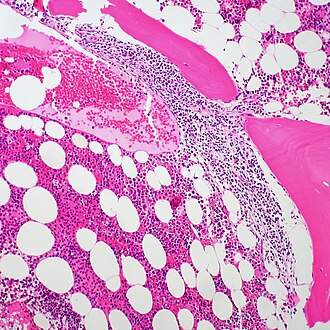

LM Lymph node: abundant abnormally-shaped lymphoid follicles with some of the following: non-polarized mantle zone, non-polarized germinal center, loss of tingible body macrophages, sinuses effaced (lost)

Microscopic

Features (lymph node):

• Abundant abnormally-shaped lymphoid follicles - key feature - including some of the following:

• Non-polarized mantle zone (normal mantle zone is usu. thicker at capsular aspect).

• Non-polarized germinal center (normal germinal center has dark & light area).

• Loss of tingible body macrophages.

• Sinuses effaced (lost).

• The intrafollicular component of the lymph node is compressed - follicles are often described as "kissing", as they nearly touch.